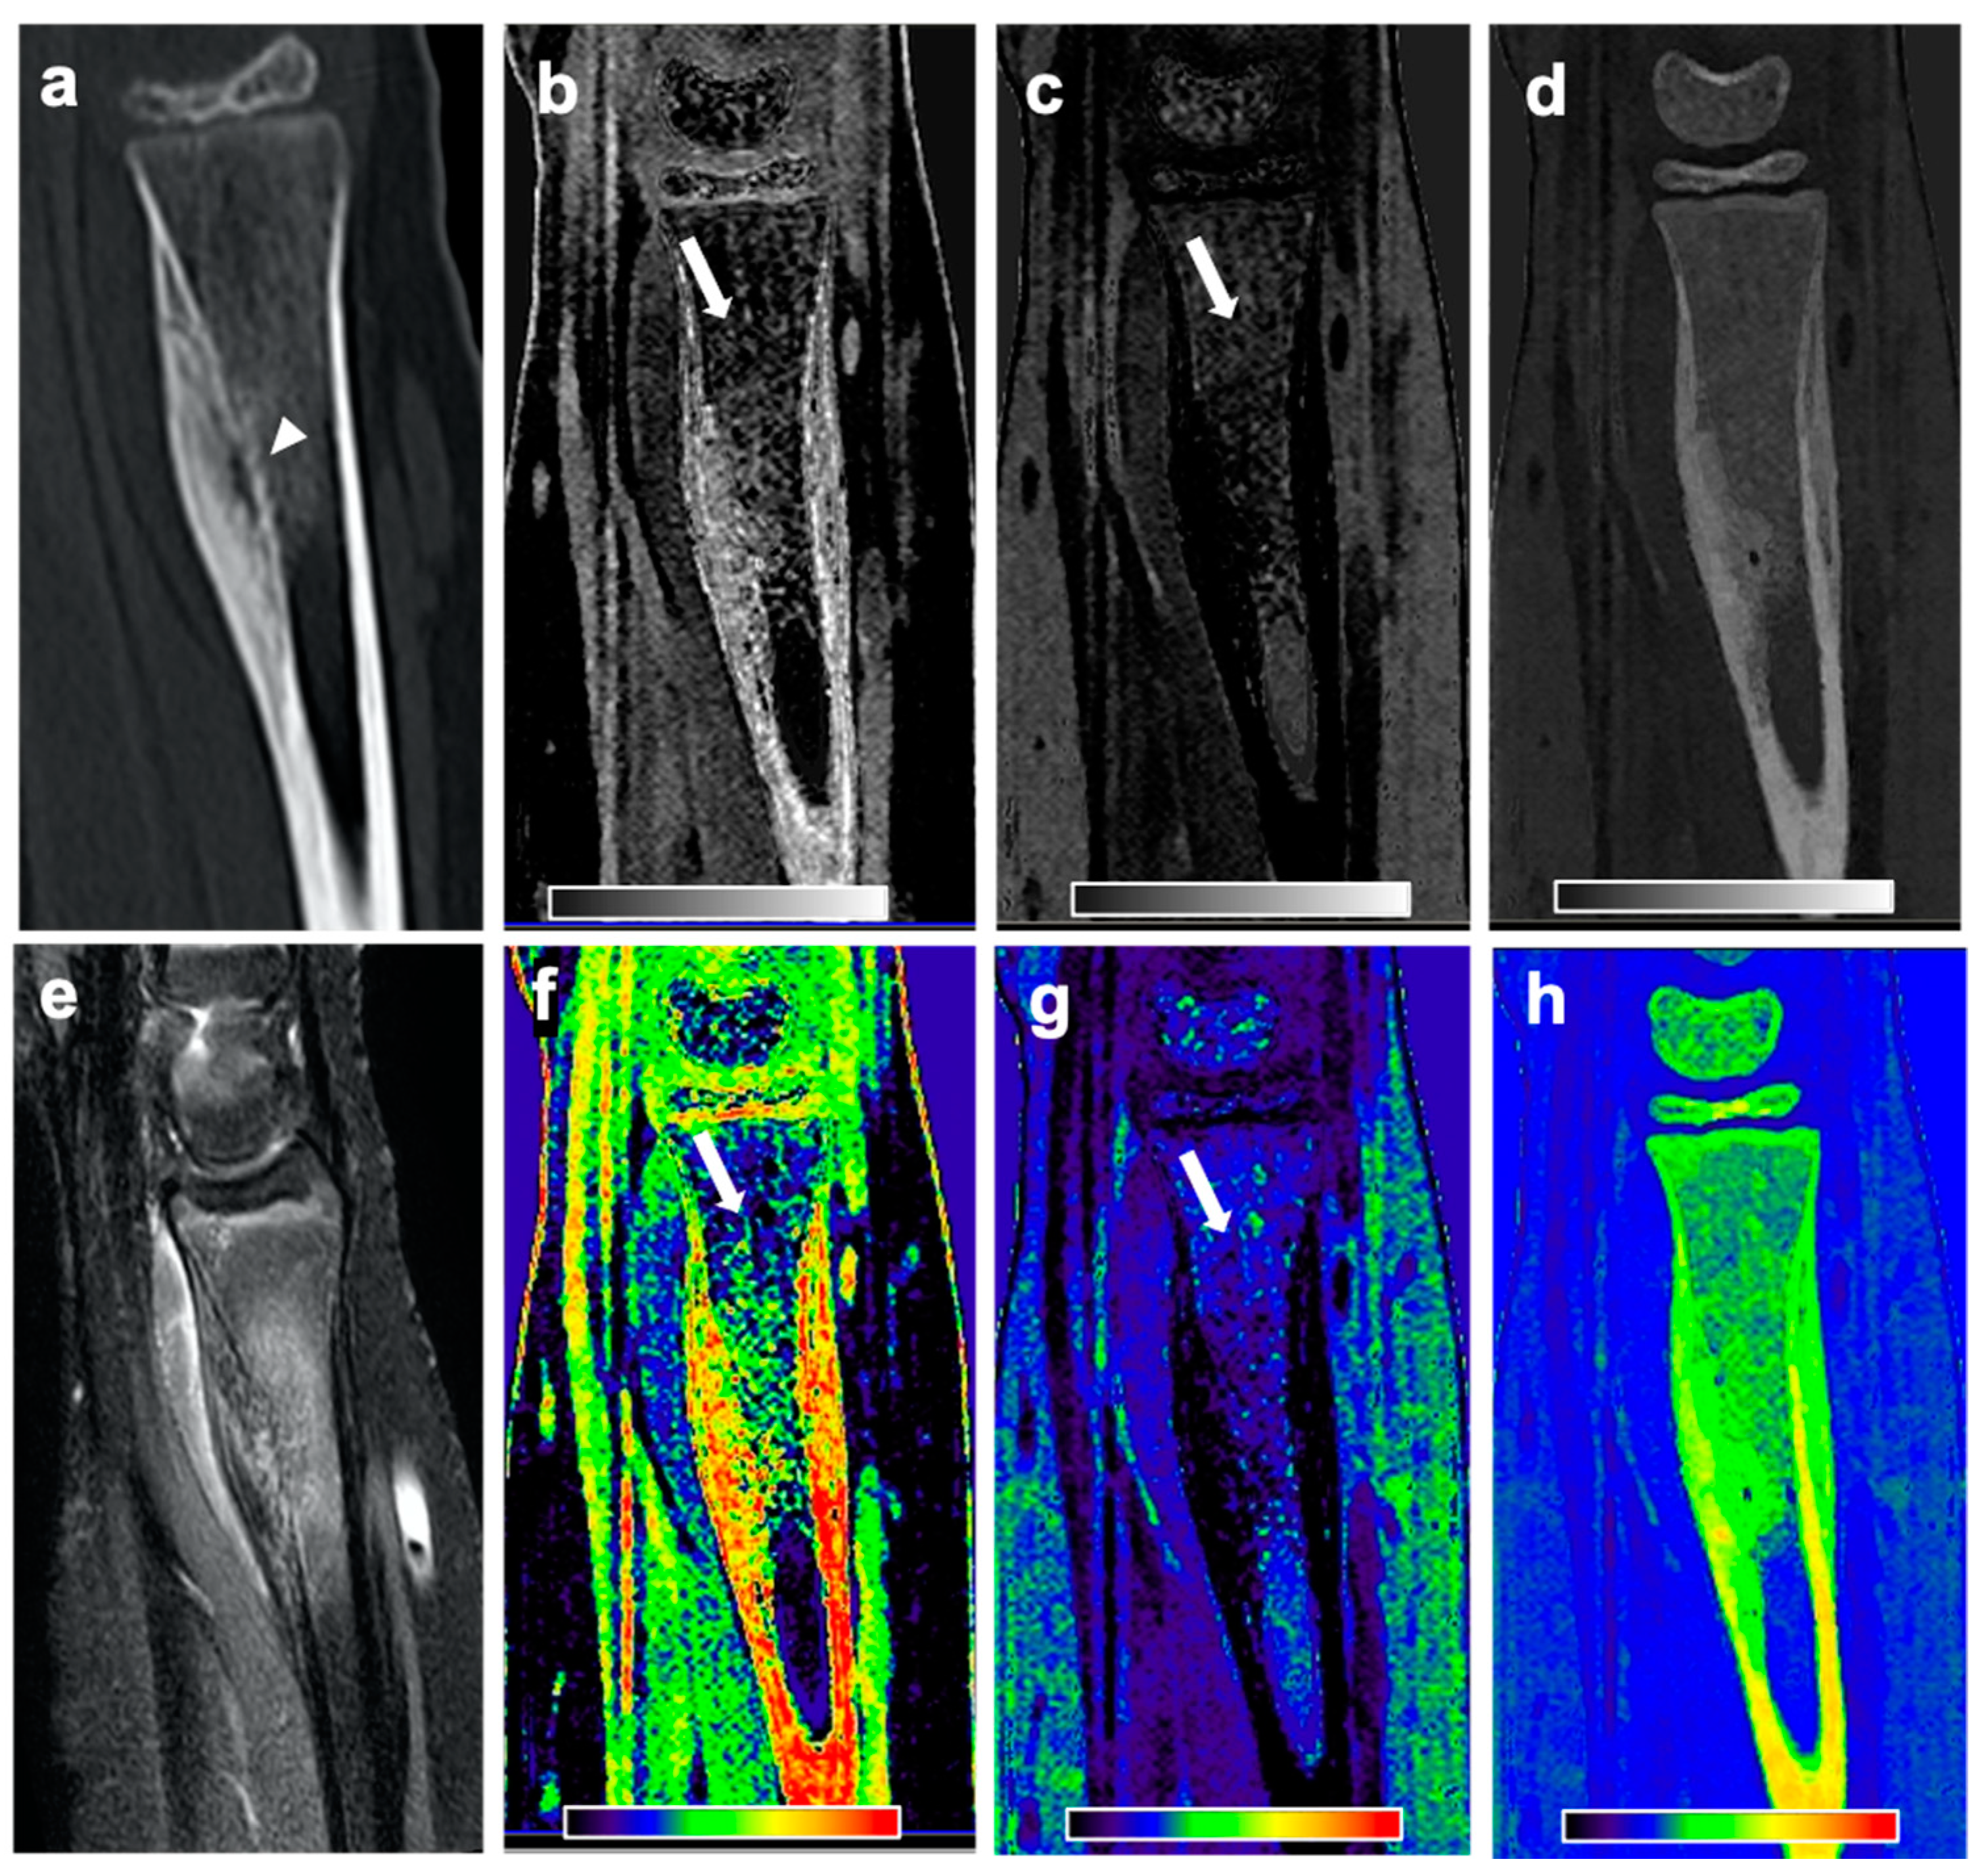

Figure 3. CT and MR images of a 12-year-old female patient with subperiosteal OO in the right distal radius. Sagittal CT reformation image (a) reveals the nidus in the right distal radius with surrounding sclerosis and a solid periosteal reaction (arrowhead). Material-specific volume fraction maps for red marrow/water (b), yellow marrow/fat (c), and hydroxyapatite (d), and respective color-coded overlays (fh) reveal an increase in water-specific volume fraction in the red-marrow map (b,f; arrow) and a decrease in fat-specific volume fraction in the yellow-marrow map (c,g; arrow) in the right femoral neck, compared to the respective area on the other side. The corresponding sagittal STIR MR image confirms the presence of an edema-equivalent signal alteration in the bone marrow around the nidus (e).